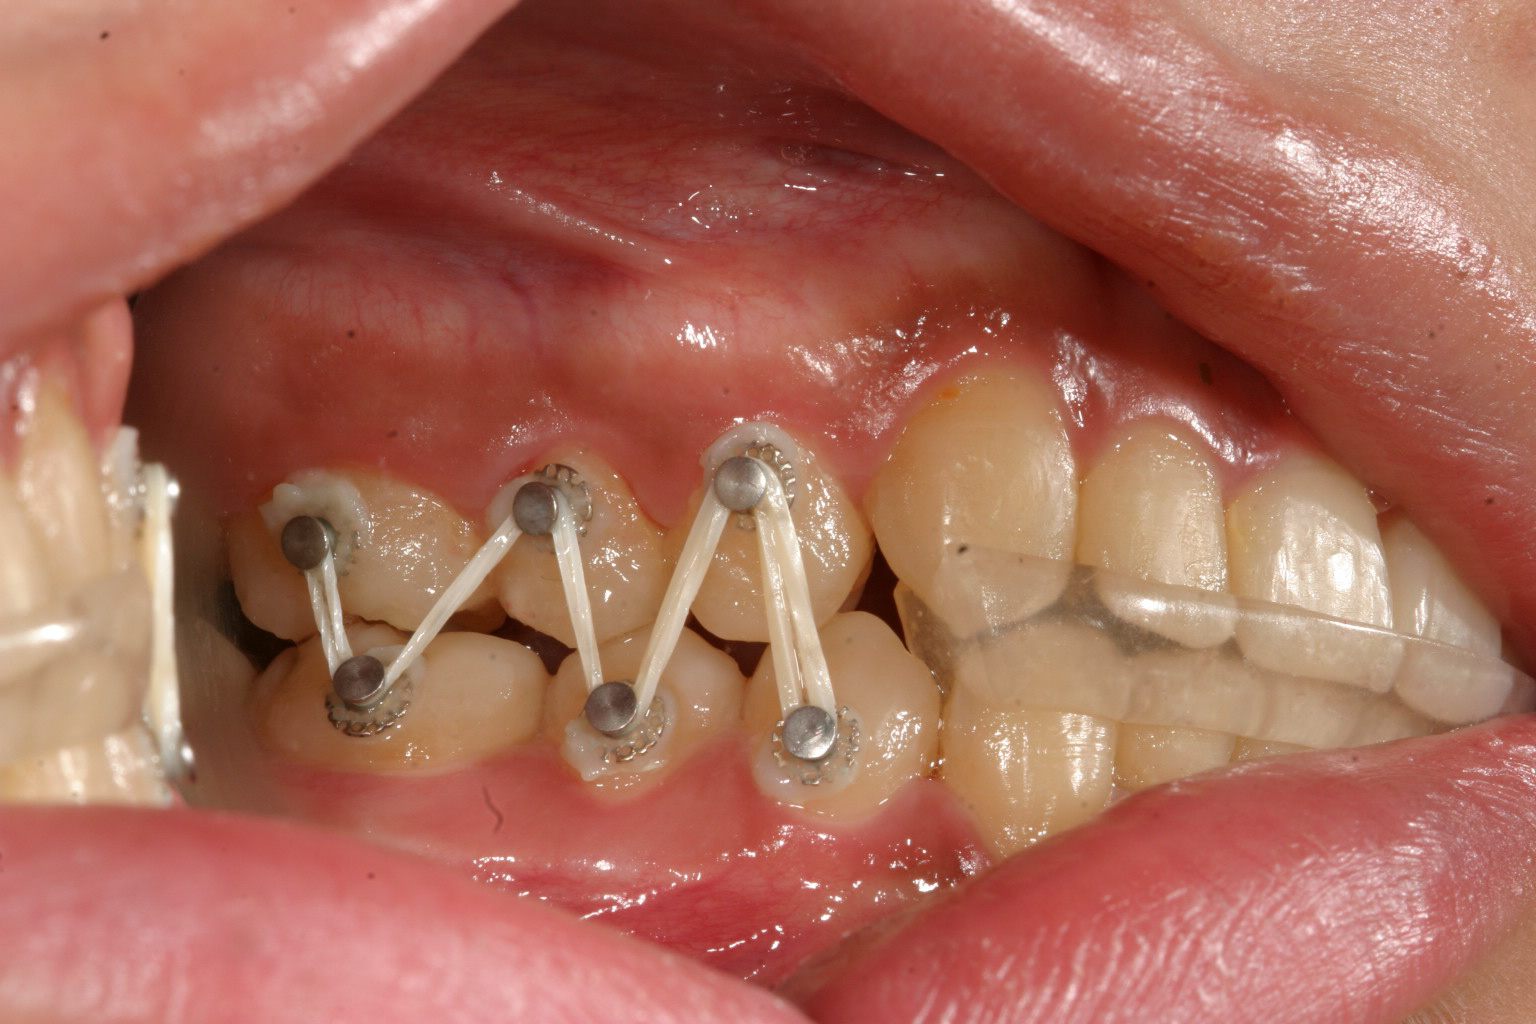

前歯に自家製のバイトアップジグを院長自ら製作しアップダウンエラスティックで臼歯の咬合を挙げてます。

右側のアップダウンエラスティックです。